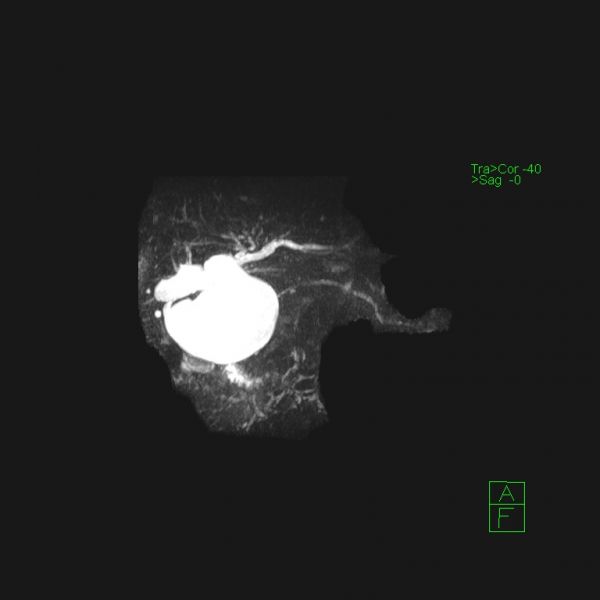

石某某,因突发上腹痛疼痛10小时入院。入院时完善急诊血常规、生化、肝功能、胰代谢以及肝胆脾增强CT等检查,考虑诊断“急性胰腺炎;胰腺假性囊肿”,进一步完善磁共振平扫+MRCP检查,确诊为胆总管囊状扩张症(Ia、C-P型)并发急性胰腺炎。首先进行胰腺炎治疗,予以禁食禁饮、抗炎、护胃、补液、抑制胰腺内外分泌、通便等治疗。经积极治疗,病情稳定后,复查生化相关指标恢复正常,王文儿主任指示:完善术前相关评估,有限期手术指征,无明显手术禁忌,于4月16日在麻醉科及护理工作人员的积极配合下成功完成全腹腔镜下胆总管囊肿剥除+胆囊切除+胆肠内引流术,术中于胆肠吻合口后方放置一18#引流管,术中生命体征平稳,术中失血量约50ml,手术历时约4.5小时,麻醉复苏成功后安返病房。

在诊疗过程中科学的诊疗决策对于患者诊治过程中的顺利推进起到举足轻重的作用。患者因上腹痛10小时入院,完善相关生化以及CT影像检查发现:第一,胰代谢异常明显,结合临床表现和影像学检查,急性胰腺炎诊断明确;第二,上腹部CT发现胰头区有囊性占位,报告:假性囊肿形成可能。王文儿主任仔细阅片以及根据发病特点分析,胰头区囊性占位极似胰腺假性囊肿,根据腹痛特点及胰代谢指标分析,最容易考虑诊断为“急性胰腺炎并假性囊肿形成”。但是,王文儿主任进一步指出:发病时间短,一般不可能在短时间内形成假性囊肿,那么就应该考虑是否还有其他病变?是否考虑胆总管囊状扩张症?那么,就需要进一步完善检查,诊断胆总管囊状扩张症最有价值的方法就是MRCP,于是完善MRCP检查后证实了王文儿主任的推断,最终患者诊断为胆总管囊状扩张症(C-P型)并急性胰腺炎。最后我们的诊疗方案分两步走:第一,积极治疗并发症。第二,待病情稳定后实施腹腔镜胆总管囊肿剥除+胆囊切除+胆肠内引流,以加速康复理念为指导,实现患者快速康复出院,赢得病人的信任。

术前影像图片